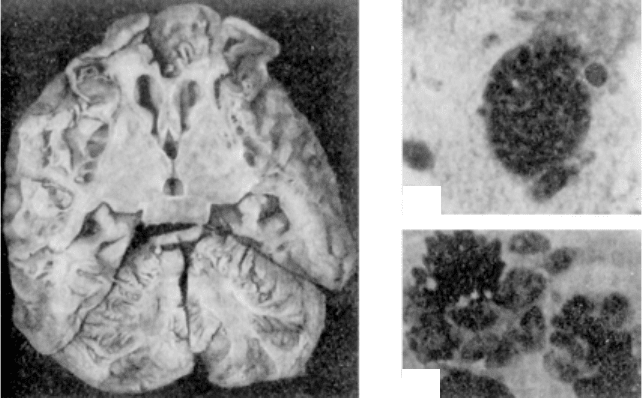

Êëàñèô³êàö³ÿ. Äèçîíòîãåíåòè÷íå ïîõîäæåííÿ á³ëüøîñò³ ïóõ-

ëèí ó ä³òåé óñêëàäíþº ¿õ êëàñèô³êàö³þ. Ç îäíîãî áîêó, ó ä³òåé

â îäí³é ³ ò³é ïóõëèí³ çóñòð³÷àþòüñÿ òêàíèíè ð³çíîãî ã³ñòîãåíåçó,

ç äðóãîãî åìáð³îíàëüíå ïîõîäæåííÿ áàãàòüîõ ïóõëèí ïåðåøêîä-

æàº çÿñóâàòè ¿õ òêàíèííó íàëåæí³ñòü. Ó çâÿçêó ç öèì êëàñèô³-

êóâàòè ïóõëèíè ó ä³òåé çà ã³ñòîãåíåòè÷íèì ïðèíöèïîì, ÿê êëà-

ñèô³êóþòü ïóõëèíè äîðîñëèõ, íå çàâæäè ìîæëèâî. ßêùî âèõîäè-

òè ç ïðèïóùåííÿ ïðî îíòîãåíåòè÷íèé ðîçâèòîê, òî âñ³ ïóõëèíè

ó ä³òåé ìîæíà ðîçïîä³ëèòè íà òðè îñíîâí³ òèïè.

Äî ïóõëèí ïåðøîãî òèïó â³äíîñÿòüñÿ òåðàòîìè,

àáî òåðàòî¿äí³, äèçîíòîãåíåòè÷í³, ïóõëèíè. Âèíèêíåííÿ òåðàòîì

ïîÿñíþþòü ïîðóøåííÿì ì³ãðàö³¿ çàðîäêîâèõ ñòàòåâèõ êë³òèí ïðè

ôîðìóâàíí³ êàóäàëüíîãî ê³íöÿ óðîãåí³òàëüíîãî ãðåáíÿ. ³äîêðåì-

ëåííÿ ÷àñòèíè íåäèôåðåíö³éîâàíèõ ñòàòåâèõ êë³òèí êàóäàëüíîãî

ê³íöÿ öüîãî ãðåáíÿ òà ¿õ ïåðñèñòóâàííÿ ïðèçâîäèòü äî ðîçâèòêó

òåðàòîìè.

Çà ã³ñòîëîã³÷íîþ áóäîâîþ ðîçð³çíÿþòü ã³ñò³î¿äí³, îðãàíî¿äí³ òà

îðãàí³çìî¿äí³ òåðàòîìè (äèâ. Ïóõëèíè). Ðîçð³çíÿþòü òàêîæ òå-

ðàòîìè, ÿê³ ðîçâèâàþòüñÿ ³ç åëåìåíò³â åìáð³îáëàñòó, åìáð³îíàëüí³